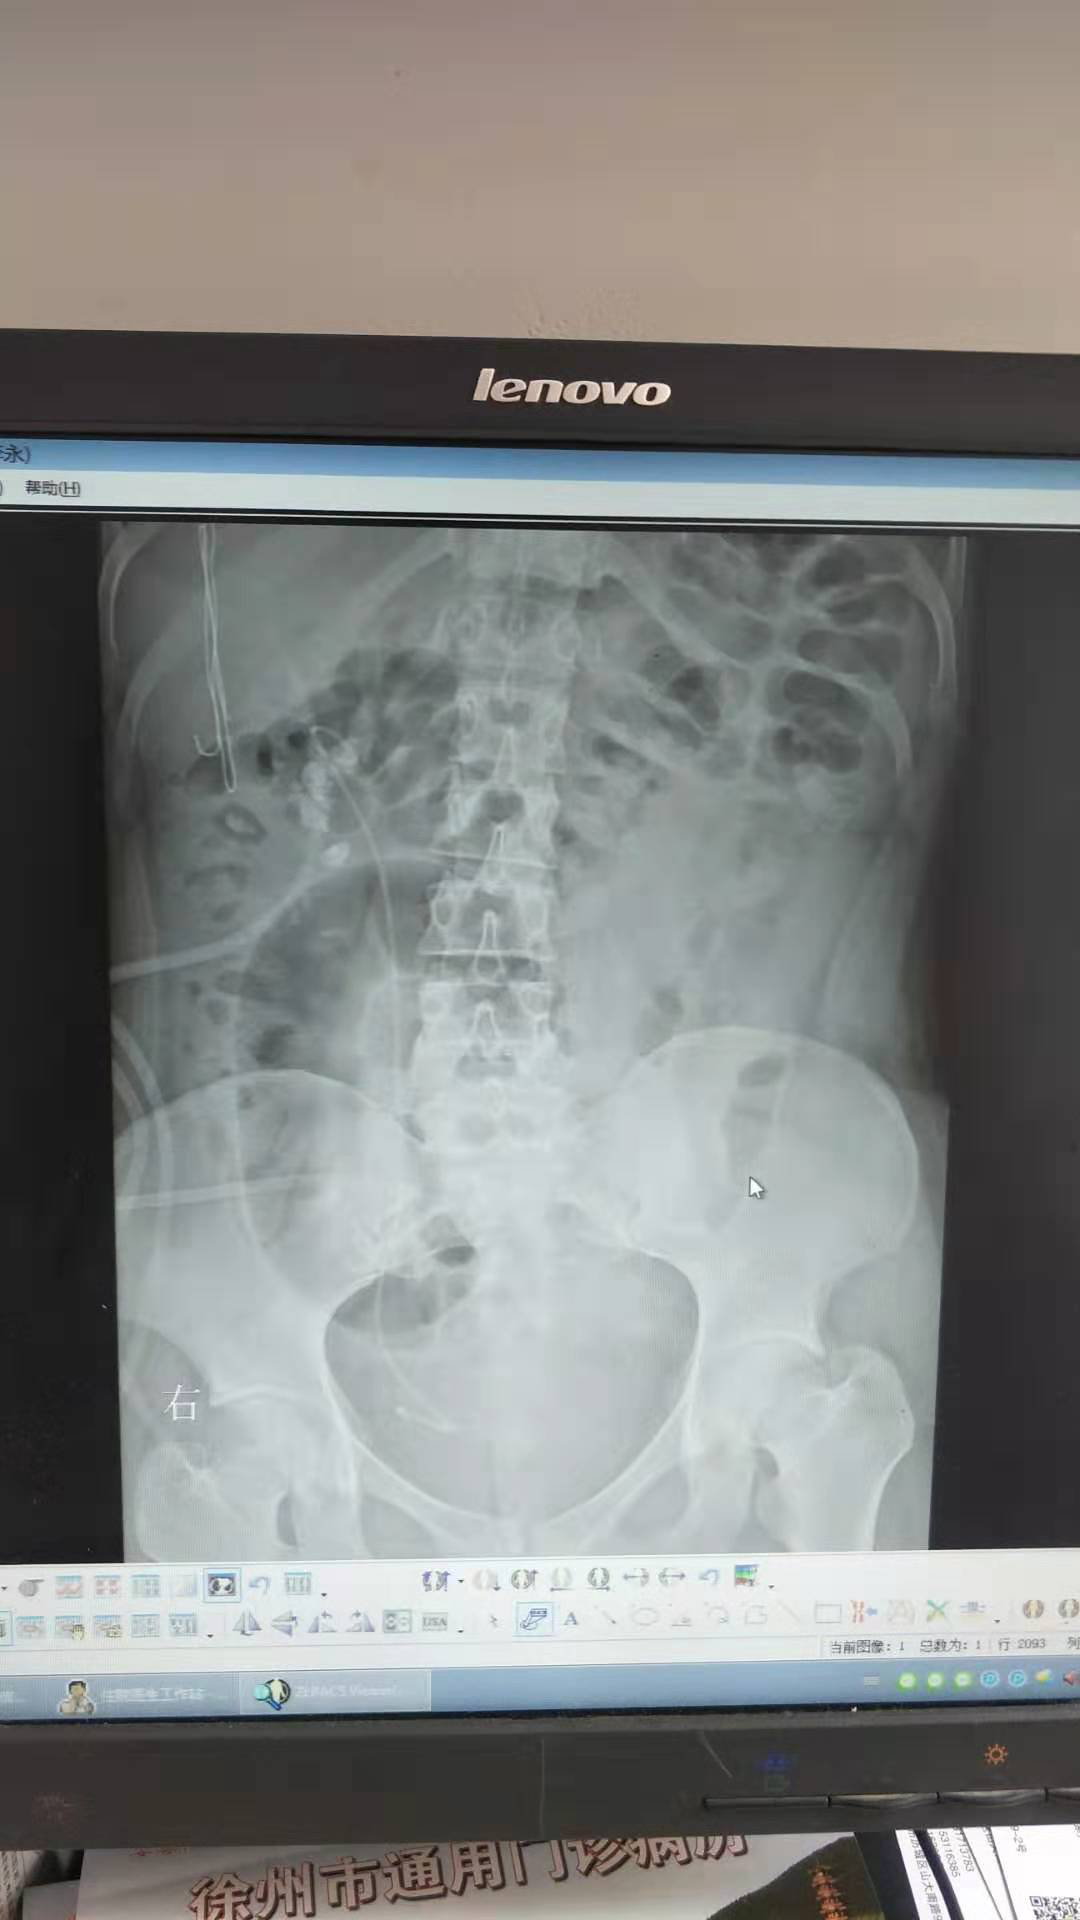

患者:王嬌,女性,21歲。因“體檢發(fā)現(xiàn)右腎結(jié)石8月余”入院,診斷為右腎多發(fā)結(jié)石、右輸尿管結(jié)石、右腎積水。于2019-07-17在全麻下行“輸尿管軟鏡聯(lián)合經(jīng)皮腎鏡右腎結(jié)石碎石取石術(shù)”, 此術(shù)式采取側(cè)仰臥奔跑位,為我科首次采用輸尿管軟鏡聯(lián)合經(jīng)皮腎鏡處理復(fù)雜性腎結(jié)石。優(yōu)點(diǎn)為軟性輸尿管鏡可以觀察和處理經(jīng)皮腎鏡不能達(dá)到的腎盂、腎盞內(nèi)的結(jié)石,配合鈥激光碎石效果滿意。對(duì)于腎臟復(fù)雜性結(jié)石清除率較高,效果良好,術(shù)后恢復(fù)快,5天后康復(fù)出院,對(duì)治療表示滿意。